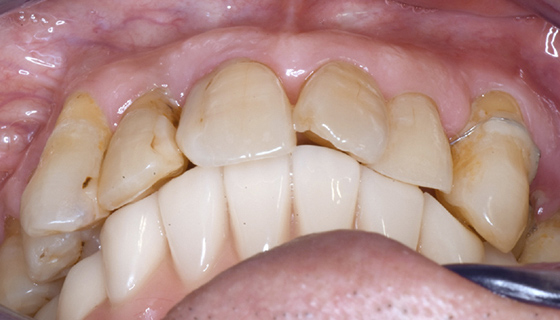

最終補綴物装着

下顎の歯がしっかりと固定され、きちんと噛めるようになりました。